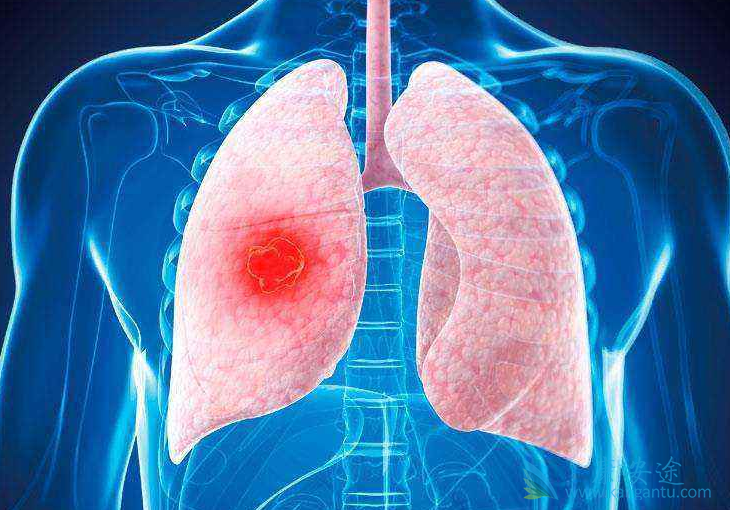

肺癌居恶性肿瘤发病第一位,每年多少人发病呢?78万人,其中男性52万,是女性的两倍。女性每年是26万,什么导致肺癌成为发病率第一的癌症,而且是男性远远多于女性呢?第一大原因是吸烟,中国烟民男性远远多于女性,所以这也是为什么说男性的发病率是女性两倍的原因。

除了吸烟以外,还有六大原因分别是:第一,氡气辐射,什么叫氡气呢?就是原子量最高的那个惰性气体,它会产生核辐射。家庭里面的氡气从哪里来呢?主要是装修建材的污染,比如说大理石,它会释放氡气,装修的时候,一定要选择好的装修材料;第二,就是石棉纤维暴露,主要是从事与石棉有关的职业的人员;第三,其他致癌物暴露,最常见的比如说柴油发动机的尾气,含有一些重金属污染,比如说铬;

第四,就是空气污染,最厉害的就是悬浮在空气中的微颗粒,也就是说,那个PM2.5是雾霾里最危险的成分。所以说,住在大马路边上的人,包括家里面经常在厨房炒菜,吸油烟的人,这些人的肺癌的发病率比普通人要高很多;第五,就是感染HIV病毒,也就是艾滋病病毒;第六,有家族史,比如说父母兄弟姐妹中有一人得过肺癌,这样的人的概率会比普通人发病率高一倍。所以,以上风险不知道大家在日常过程中会接触到几项。总之,要学会分辨,多加防范。养成良好的生活习惯。